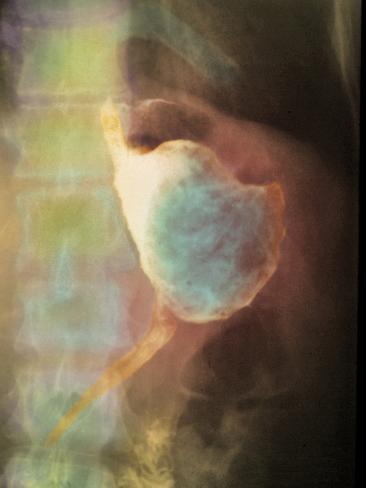

Images of Stomach Cancer Treatment

Pictures of Stomach Cancer Treatment

Stomach Cancer Treatment Photos

Stomach Cancer Treatment Pictures

Photos of Stomach Cancer Treatment

Stomach Cancer Treatment Images